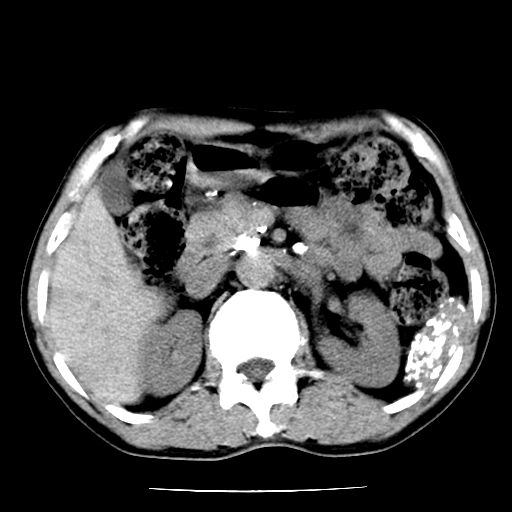

男,59岁,“结核性胸膜炎”30余年,胸部经常疼痛,多次x检查提示“肺部”炎症。腹部疼痛5日,b超提示:“肝内短管结石,余显示不清,建议进一步检查。”

两肺结核并右侧胸腔积液;脾脏、腹腔及腹膜后淋巴结结核[陈旧性];肝内胆管结石

胸部腹部都是结核(双肺。纵隔淋巴结,肝脏,脾脏,肠系膜)

两肺结核并右侧胸腔积液;脾脏、腹腔及腹膜后淋巴结结核[陈旧性];肝内胆管结石。直肠息肉?